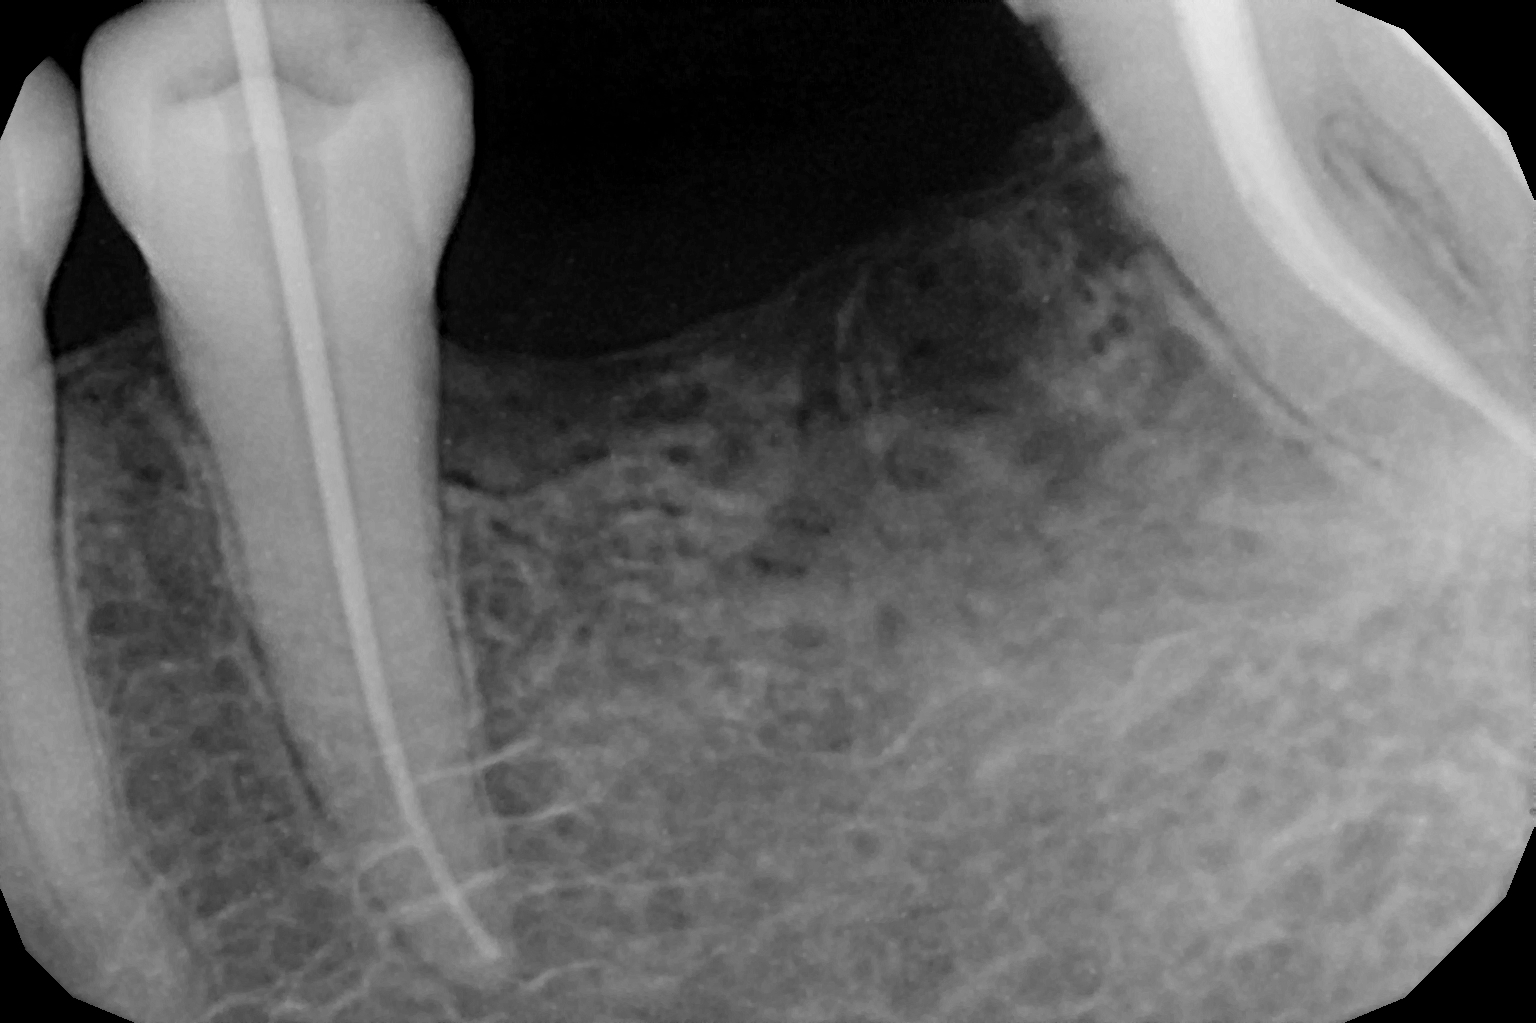

When the tooth is is sensitive to particularly hot and cold. When you cannot chew from that side or there is associated action of pain and swelling with same tooth, root canal treatment can save the tooth. For root canal treatment our clinic is equipped with state-of-the-art facility. We are following the protocol that is universally accepted and considered as a gold standard We are using rubber Dam for maximum possible cases. The root canal treatment is done under local anaesthesia that's why mostly it is painless . The rubber Dam isolation helps in proper irrigation and it provides much needed ease to the operating dental surgeon and the patient . The sealer and filling material are one of the Prime requisite of quality root canal treatment, it needs use of multiple X rays to really judge whether the results are acceptable or not. In older days root canal was just about cleaning the decade portion, removing the Pulp and filling it with biocompatible material but nowadays the root canal treatment it is very much advanced the precision is increased manifold. The materials and armamentarium that is required for efficient root canal have advanced in exclusion initial ways the the Abstract of all these things is the patients are getting great results after root canal treatment. Only the root canal is not sufficient to make a tooth functional again ,it needs use of Core buildup material and complete coverage Crowns according to the tooth position. During Covid19 time we have studied and implemented use of of high strength composites in our practice and the results of it are amazing many times it has saved tooth from being restored with crown. In some cases where the tooth is grossly carious we need a complete coverage crown. The materials and the Crown materials are are available in various price ranges. We prefer only the best of materials for our patients. We believe that to perform best treatment we need best of the armamentarium and best of the material for our patients who value and deserve the best of the treatment.